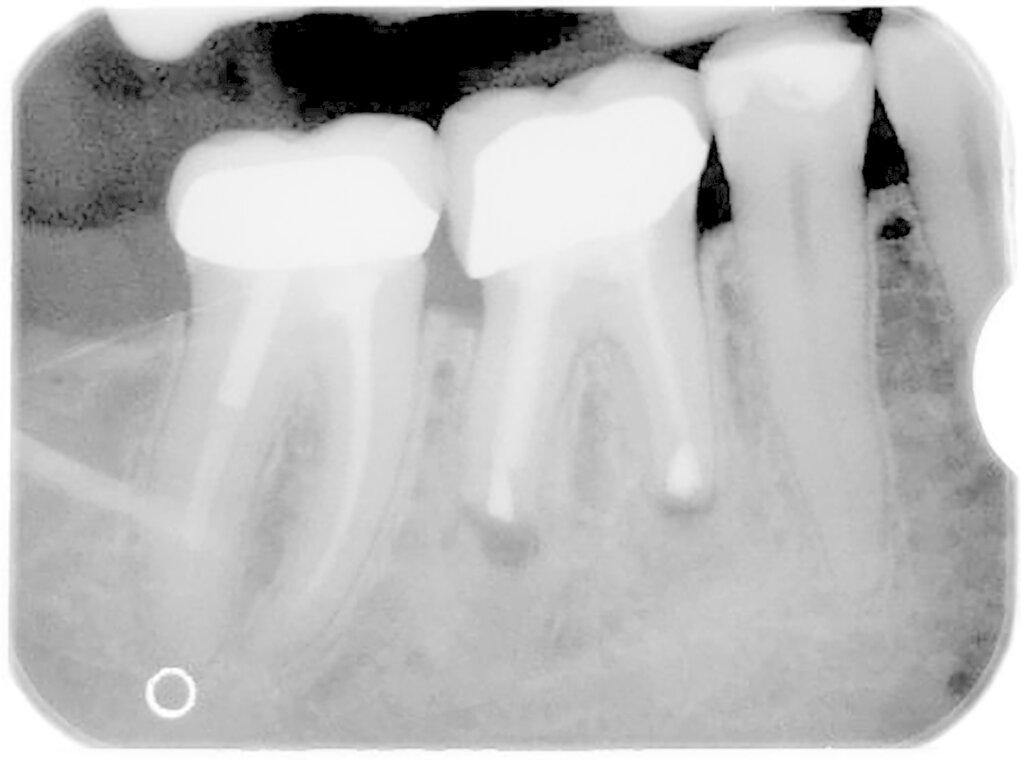

Eine präoperative akute klinische Symptomatik in Form von Schmerzen, Perkussionsempfindlichkeit, einer Schwellung oder einem Abszessgeschehen ist mit einer signifikant schlechteren Prognose des Zahns vergesellschaftet. Gleiches gilt für das Vorhandensein einer Fistel bei chronischem Verlauf. Zähne, die zum ersten Mal einer WSR unterzogen werden, haben eine signifikant bessere Prognose als Zähne mit einer Revision der WSR. Ein weiterer wichtiger prognostischer Faktor sind retentive Wurzelstifte (Abbildung 3). Die besondere Problematik bei diesen Zähnen liegt oftmals in der erschwerten Möglichkeit der apikalen Abdichtung, wenn der Stift bis zum Neoapex reicht. Infolgedessen werden die Wurzeln oft weniger stark gekürzt, um noch ausreichend Wurzelkanal für die retrograde Wurzelfüllung zu haben. Zum anderen werden in dieser Gruppe auch in der Folgezeit Wurzelfrakturen häufiger beobachtet. Dies scheint insgesamt von Relevanz zu sein, denn diese Zähne haben ebenfalls eine signifikant schlechtere Prognose. Zähne mit einer Stiftperforation stellen ohnehin eine Kontraindikation für eine WSR dar und sind hier gar nicht berücksichtigt.